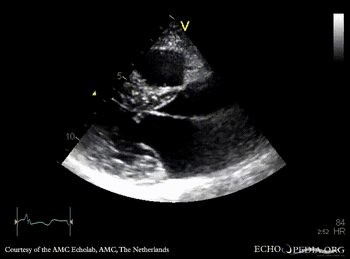

PLAX: concentric hypertrophy of left ventricle, SAM of AMVL PLAX with Color Doppler: high velocity turbulent flow in LVOT